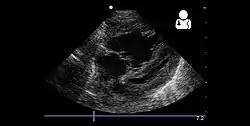

Echocardiography

If pulmonary hypertension is suspected based on the above assessments, echocardiography is performed as the next step.[10][11][53] A meta-analysis of Doppler echocardiography for predicting the results of right heart catheterization reported a sensitivity and specificity of 88% and 56%, respectively.[55] Thus, Doppler echocardiography can suggest the presence of pulmonary hypertension, but right heart catherization (described below) remains the gold standard for diagnosis of PAH.[10][11] Echocardiography can also help to detect congenital heart disease as a cause of pulmonary hypertension.[10]

- 4 month old with pulmonary hypertension as seen on ultrasound[56]

4 month old with pulmonary hypertension as seen on ultrasound[56]- Long standing pulmonary hypertension[57]